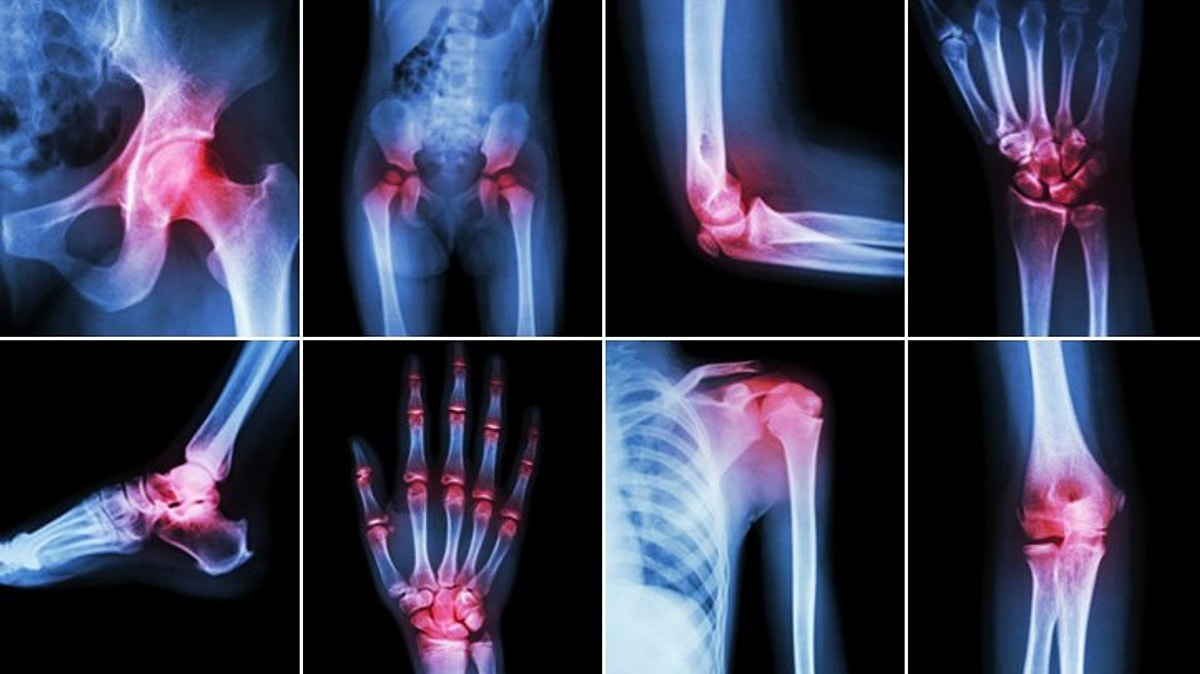

Диагностика ревматоидного артрита

Современная диагностика РА основывается на сочетании клинических данных, лабораторных анализов и инструментальных методов исследования. В 2025 году использование высокоточных технологий позволяет выявлять заболевание на доклинической стадии, что существенно улучшает прогноз.

3. Инструментальная диагностика

• рентгенография: Помогает выявить изменения в суставах на поздних стадиях, например эрозию костей и сужение суставной щели;

• УЗИ суставов: Используется для оценки воспаления и повреждения тканей;

• МРТ: Позволяет детально изучить состояние суставов и окружающих тканей на ранних стадиях.